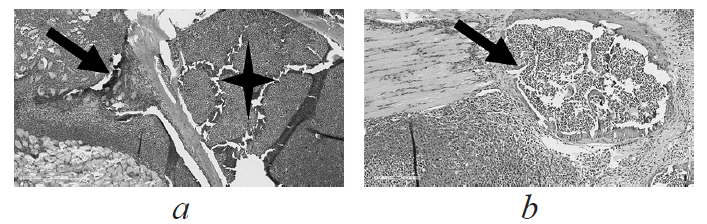

При гистологическом исследовании органов мышей с трансплантированой взвесью эпидермоидной карциномы легких Льюиса выявлен ряд общих признаков. Опухолевый узел характеризовался обширными зонами некроза опухоли, деструкцией мышечной ткани и зонами инвазии костных пластинок, без признаков проникновения в костномозговую полость (рис. 3).

Рис. 3. Гистологическое исследование опухолевого узла мышей-опухоленосителей, не инфицированных туберкулезом (×200, гематоксилин и эозин): a — бедренная кость; b — мягкие ткани бедра. Стрелкой показаны опухолевые структуры, звездочкой помечена костномозговая полость

Fig. 3. Histological examination of the tumor node of a tumor-bearing mice not infected with TB (×200, Hematoxylin and eosin): a — the femur; b — the soft tissue of the thigh. The arrow shows tumor structures, the asterisk marks the bone marrow cavity